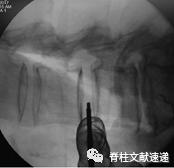

图示:术中透视图像显示腹膜后间隙剥离和腰大肌前腹后部活动。红色箭头表示运动方向。